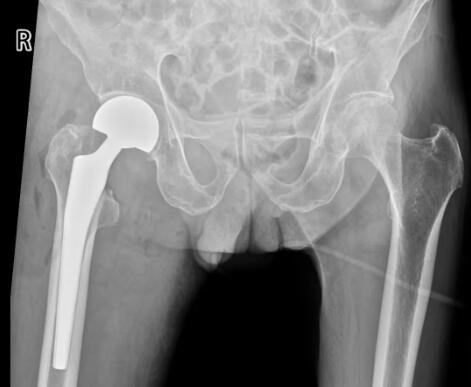

走路像针扎!30 岁小伙突遇双侧股骨头坏死,知道这些,抓住治疗的好时机!

多孔钛金属笼“撑”起坏死股骨头

真能忍!5岁生病,40岁股骨头坏死,厕所都上不了!医生:有些疼痛不是忍忍就好

幸福会迟到但永远不会缺席人的一生中走路、活动、劳动都离不开关节的支撑其中的髋关节连接大腿骨和骨盆全身受力最重因为用得多也成了最易受伤的部位一旦受伤轻则坐、站都难受重则连走路都无法进行不少患者甚至需要置换髋关节一切都源于5岁时的那场病今天故事的主人公是郑州58岁的郭大叔。他在5岁时患上了髋关节炎,因为当时治疗条件有限,经过简单治疗后恢复,但右下肢不如左下肢灵活。郭大叔在郑州一家纺织厂上班,年轻时工作......